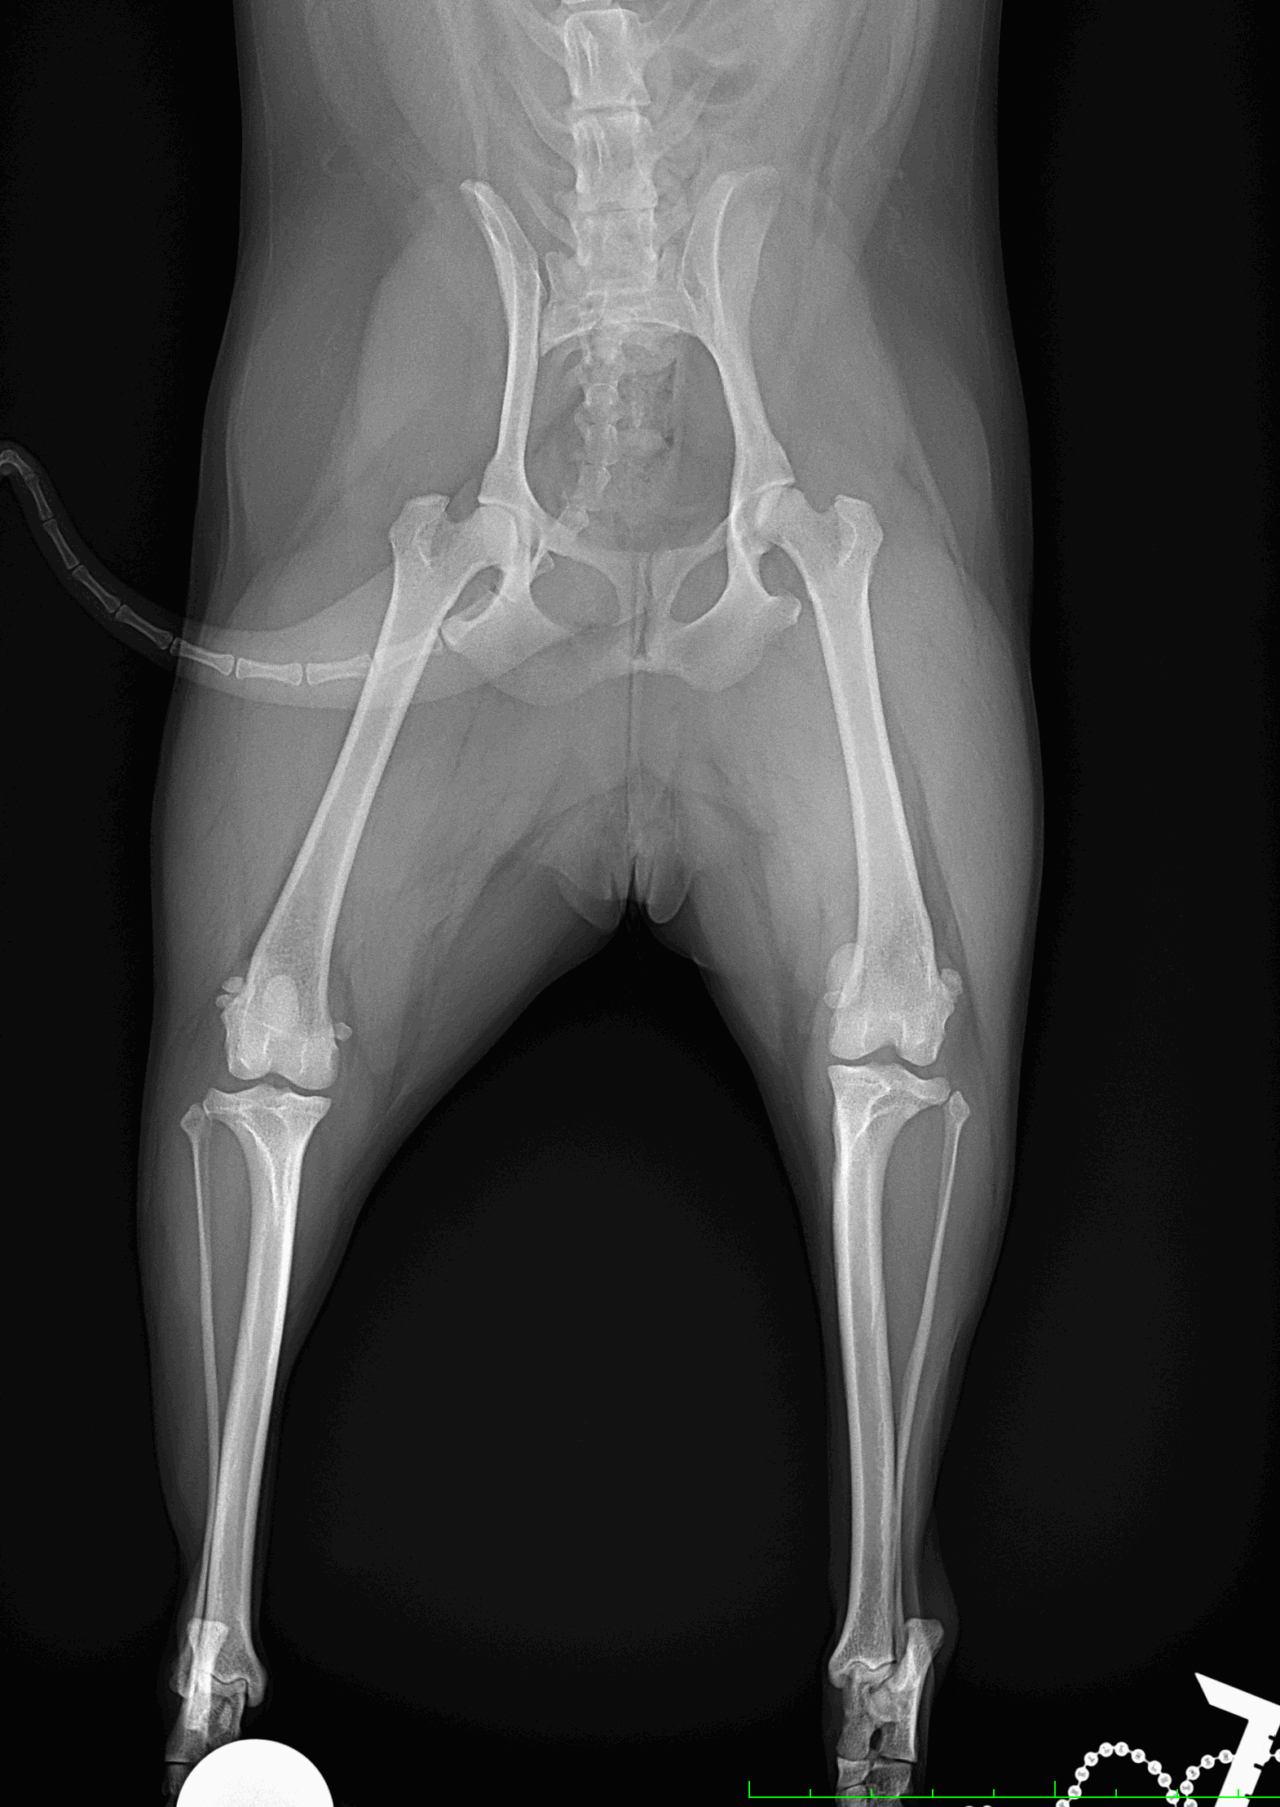

膝蓋骨内方脱臼G3

ポメさんがソファーからジャンプした後から急性の跛行を呈しているとのこと。もともと存在していた膝蓋骨内方脱臼が憎悪した可能性があります。ブロックリセッション大腿骨滑車深化術、脛骨粗面外側移行術、関節包の縫縮で対応しました。しばらく安静が必要です。